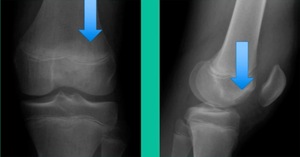

43-Year-Old, symptomatic medial femoral condyle.

D1 football player formally, affecting ADLs. For this one, I initially just wanted to watch it. This looks pretty small when he came in. Let’s see what happens. Six months later, this is where he progressed to.

We get in there, it’s delaminated, not much bone, nothing to fix in my mind, and so we drilled it.

How do these do? There’s actually reasonable data for marrow stimulation for OCD. But if you have the option for small defects, I would prefer an osteochondral allograft over microfracture based on the literature. That’s the take-home. Marrow stimulation, if you do it, you’re probably better off drilling it. We showed that we could reduce revision rates with marrow stimulation by two-thirds if you drill it versus use a microfracture awl.